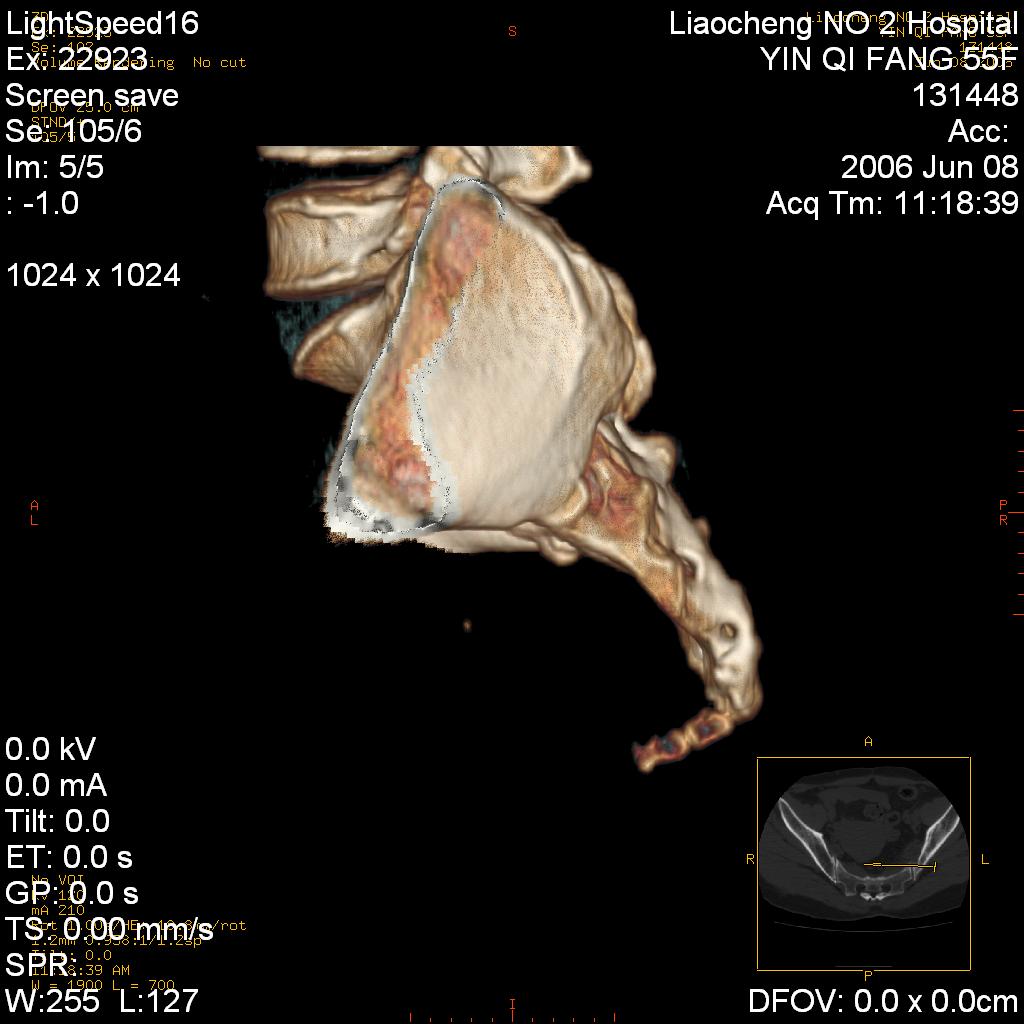

女,55岁,十余年前骶尾骨摔伤,x线平片诊断骶骨裂纹骨折,现在骶尾部又疼痛2月,x线怀疑骶骨左下部骨质破坏。大家看看,是不是先天变异。正常人不是只有4个骶孔吗?怎么此病例有5个?

两侧骶髂关节炎,确实做得很漂亮

众口一词啊,图象确实漂亮,羡煞人也!右侧骶髂关节间隙变窄,相对缘增生硬化,髂骨侧增生明显。左侧轻微类似改变,考虑双侧骶髂关节炎。余未见异常。

考虑双侧骶髂关节炎。余未见异常。

支持骶髂关节炎,3d做得很漂亮!!!!